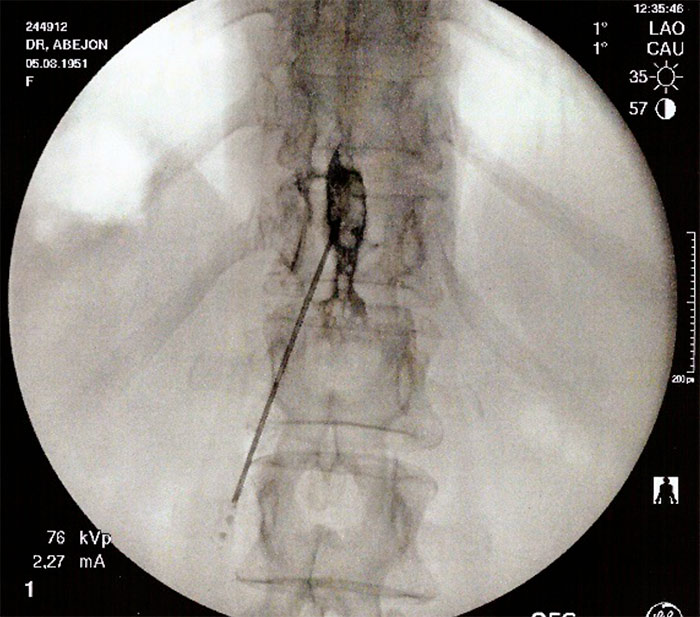

Se infiltra la piel con anestésico local (5-10 ml de lidocaína 1%) y después se hace la técnica epidural con una aguja tuohy 18-20G. Después de atravesar la piel se avanza la aguja inclinándola levemente hacia superior y medial para hacer contacto con la lámina. Una vez alcanzada la lámina se retira el fiador y se conecta la jeringa de baja resistencia; luego se redirige la aguja dándole una angulación de 45° en el plano sagital y 15° hacia medial; antes de avanzar se debe comprobar con el rayo en lateral que la aguja se encuentra entre las dos apófisis espinosas. Se recomienda también seguir avanzando lentamente y con guía fluoroscópica para evitar el daño medular directo con la aguja.

Una vez se nota la pérdida de resistencia se inyecta contraste y se debe dibujar una línea en la base de ambos procesos espinosos, con el rayo aún en posición lateral.